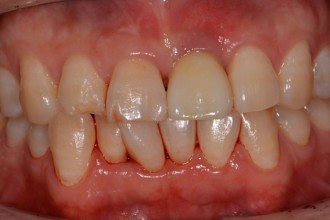

임플란트